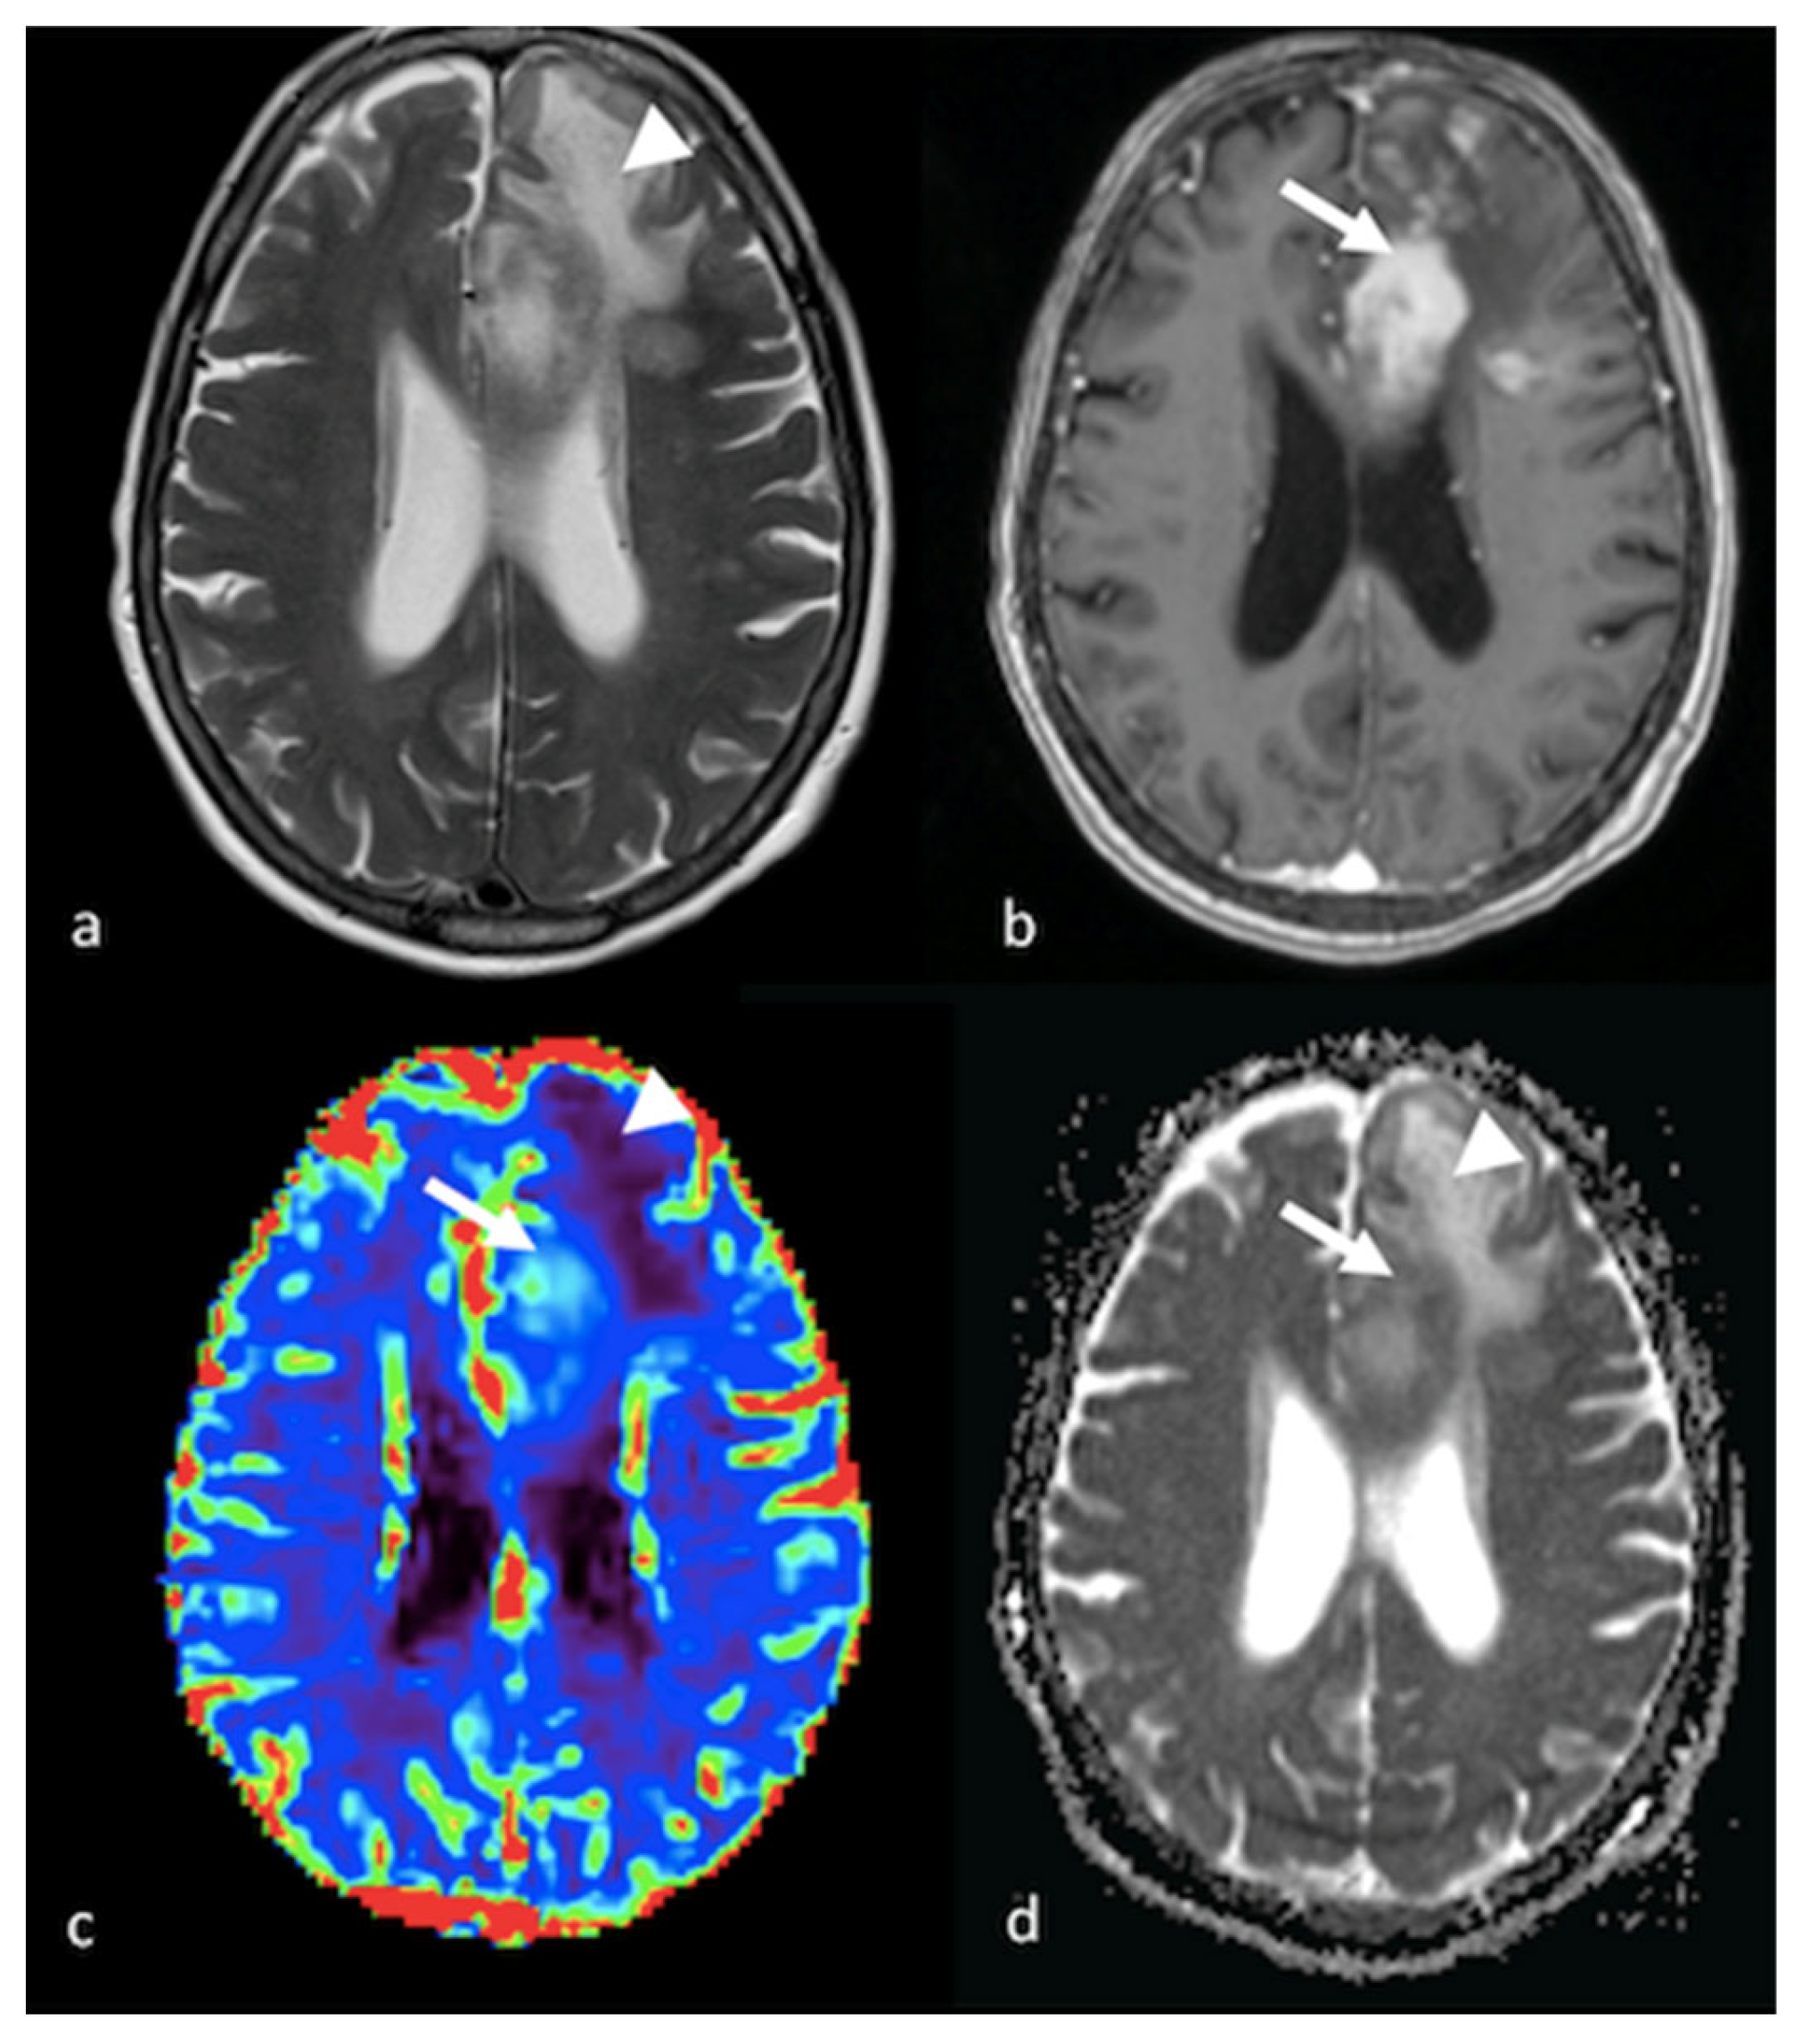

3.3.1. Dynamic Susceptibility Contrast-Enhanced Perfusion

- Halshtok Neiman, O.; Sadetzki, S.; Chetrit, A.; Raskin, S.; Yaniv, G.; Hoffmann, C. Perfusion-weighted imaging of peritumoral edema can aid in the differential diagnosis of glioblastoma mulltiforme versus brain metastasis. Isr. Med. Assoc. J. 2013, 15, 103–105. [Google Scholar] [PubMed]

- Neska-Matuszewska, M.; Bladowska, J.; Sasiadek, M.; Zimny, A. Differentiation of glioblastoma multiforme, metastases and primary central nervous system lymphomas using multiparametric perfusion and diffusion MR imaging of a tumor core and a peritumoral zone-Searching for a practical approach. PLoS ONE 2018, 13, e0191341. [Google Scholar] [CrossRef]

- Blasel, S.; Jurcoane, A.; Franz, K.; Morawe, G.; Pellikan, S.; Hattingen, E. Elevated peritumoural rCBV values as a mean to differentiate metastases from high-grade gliomas. Acta Neurochir. 2010, 152, 1893–1899. [Google Scholar] [CrossRef] [PubMed]

- Mangla, R.; Kolar, B.; Zhu, T.; Zhong, J.; Almast, J.; Ekholm, S. Percentage signal recovery derived from MR dynamic susceptibility contrast imaging is useful to differentiate common enhancing malignant lesions of the brain. AJNR Am. J. Neuroradiol. 2011, 32, 1004–1010. [Google Scholar] [CrossRef]

- Ma, J.H.; Kim, H.S.; Rim, N.J.; Kim, S.H.; Cho, K.G. Differentiation among glioblastoma multiforme, solitary metastatic tumor, and lymphoma using whole-tumor histogram analysis of the normalized cerebral blood volume in enhancing and perienhancing lesions. AJNR Am. J. Neuroradiol. 2010, 31, 1699–1706. [Google Scholar] [CrossRef]

- Lin, L.; Xue, Y.; Duan, Q.; Sun, B.; Lin, H.; Huang, X.; Chen, X. The role of cerebral blood flow gradient in peritumoral edema for differentiation of glioblastomas from solitary metastatic lesions. Oncotarget 2016, 7, 69051–69059. [Google Scholar] [CrossRef] [PubMed]